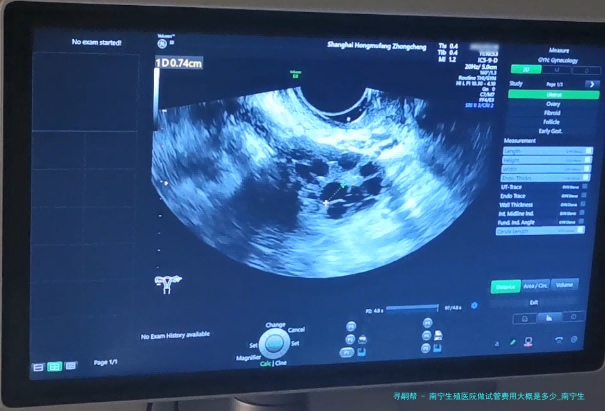

南宁生殖医院做试管费用大概是好多?试管婴儿已然成为许多不孕夫妻实现生育愿望的重要方法其中之一。南宁生殖医院作为专门从事辅助生殖医学的医疗机构,为不孕夫妇提供了精良的试管婴儿服务。如此南宁生殖医院做试管费用大概是几何呢?接下来将细致说明。

下方是南宁生殖医院区分试管项目的详细费用参考表。

项目费用(元)

基本治疗费5000-10000

辅助检查和药品费3000-5000

手术器械使用费2000-3000

麻醉师操作费500-1000

请关注,之上费用仅作参考,具体费用于南宁生殖医院实际收费为准。